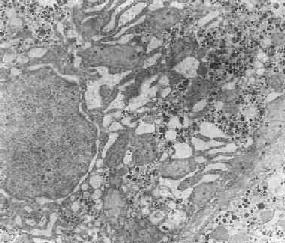

1.初级溶酶体为除水解酶类外不含其他物质并尚未参与细胞内消化过程的溶酶体,例如中性粒细胞中的嗜天青颗粒、嗜酸性细胞中的颗粒以及巨噬细胞和一些其他细胞中的高尔基小泡(图1-13)。

图1-13 初级溶酶体

图中央及中下方之卵圆形电子致密小体,外围单层包膜。(图中及下部片层状膜性结构为粗面内质网(正常肝细胞)×12000